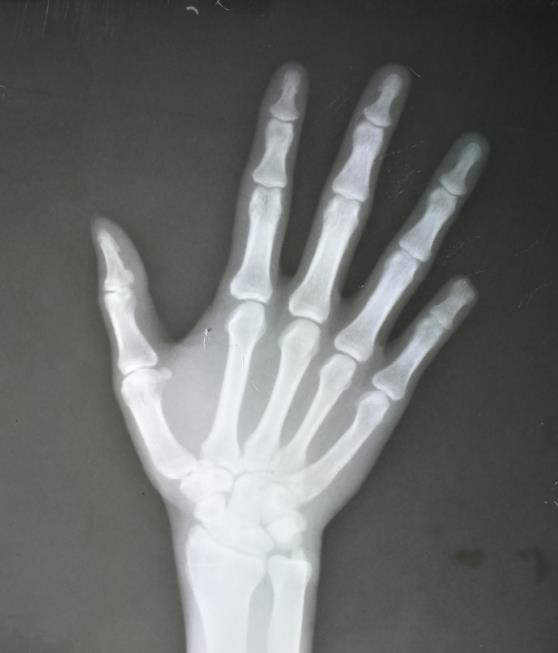

葫芦岛中医正骨诊所从网上看到了我司的便携式DR的宣传视频便来询问,客户问视频中这款便携式DR拍摄效果怎么样,每台X光机设备都有它限定的拍摄范围, 先需要弄清楚客户主要的拍摄部位,客户说他是 家正骨诊所平时对四肢拍摄的会比较多,如果是拍摄四肢的话这台便携式DR的拍摄效果是非常好的,给客户发送几张用便携式DR拍摄的四肢效果图,客户看后非常满意图像很清晰,比之前水洗胶片的效果好很多,紧接着客户又问了 些产品参数问题,经过沟通客户订购了 台。